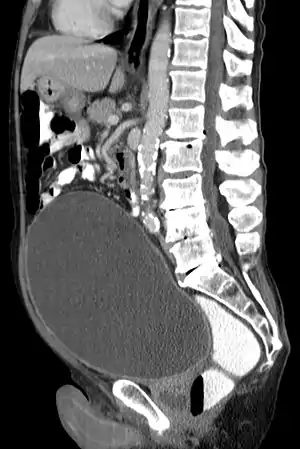

Urinary retention with greatly enlarged bladder as seen by CT scan.

As seen on axial CT

Analysis of urine flow may aid in establishing the type of micturition (urination) abnormality. Common findings, determined by ultrasound of the bladder, include a slow rate of flow, intermittent flow, and a large amount of urine retained in the bladder after urination. A normal test result should be 20-25 mL/s peak flow rate. A post-void residual urine greater than 50 ml is a significant amount of urine and increases the potential for recurring urinary tract infections. In adults older than 60 years, 50-100 ml of residual urine may remain after each voiding because of the decreased contractility of the detrusor muscle.[4] In chronic retention, ultrasound of the bladder may show massive increase in bladder capacity (normal capacity is 400-600 ml).